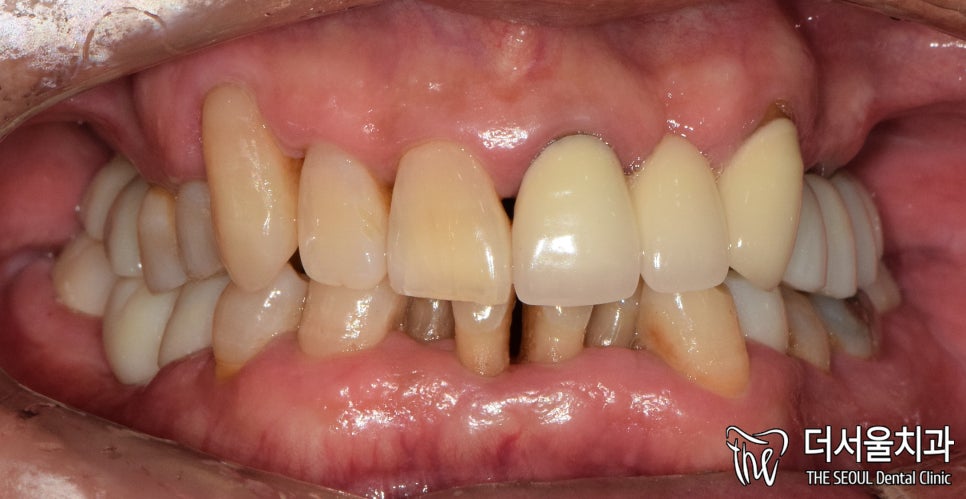

성남 치과는 정면을 먼저 눈으로 확인했습니다.

상태가 많이 좋지 않았습니다.

뼈 소실 또한 큰 것으로 보여집니다.

뼈이식을 추천 드리게 될 것이라 예측되는데요.

교합면을 보면 뼈가 고르지 않고

조금 편평하게 변한 것을 볼 수 있죠.

임플란트 수술을 진행함에 있어

살짝 난항이 있을 것이라 예측되었습니다.